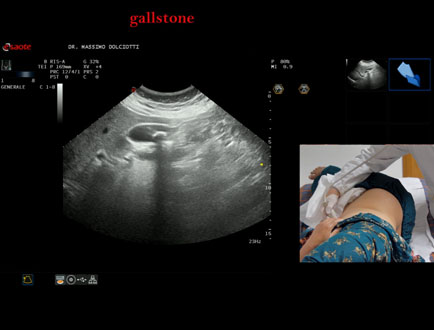

Data inserimento: 13/10/2025

Ecografia del: 07/10/2025

Strumento: Esaote MyLab Eight

Sonda: Convex Multifrequenza 1-8 MHz

Età Paziente: F 49 anni

Motivazione dell'esame: follow up per litiasi della colecisti dopo trattamento con acido ursodesossicolico.

Commento all'esame: le immagini ed il video documentano nel lume della colecisti, immagine iperecogena, delle dimensioni di 16,1 mm, con cono d'ombra posteriore, mobile al decubito, da ricondurre a litiasi.

Conclusioni: litiasi della colecisti (gallstone).

Presentazione: Dr. Massimo Dolciotti - Ancona

Elaborazione digitale: Andrea Dini - Ancona